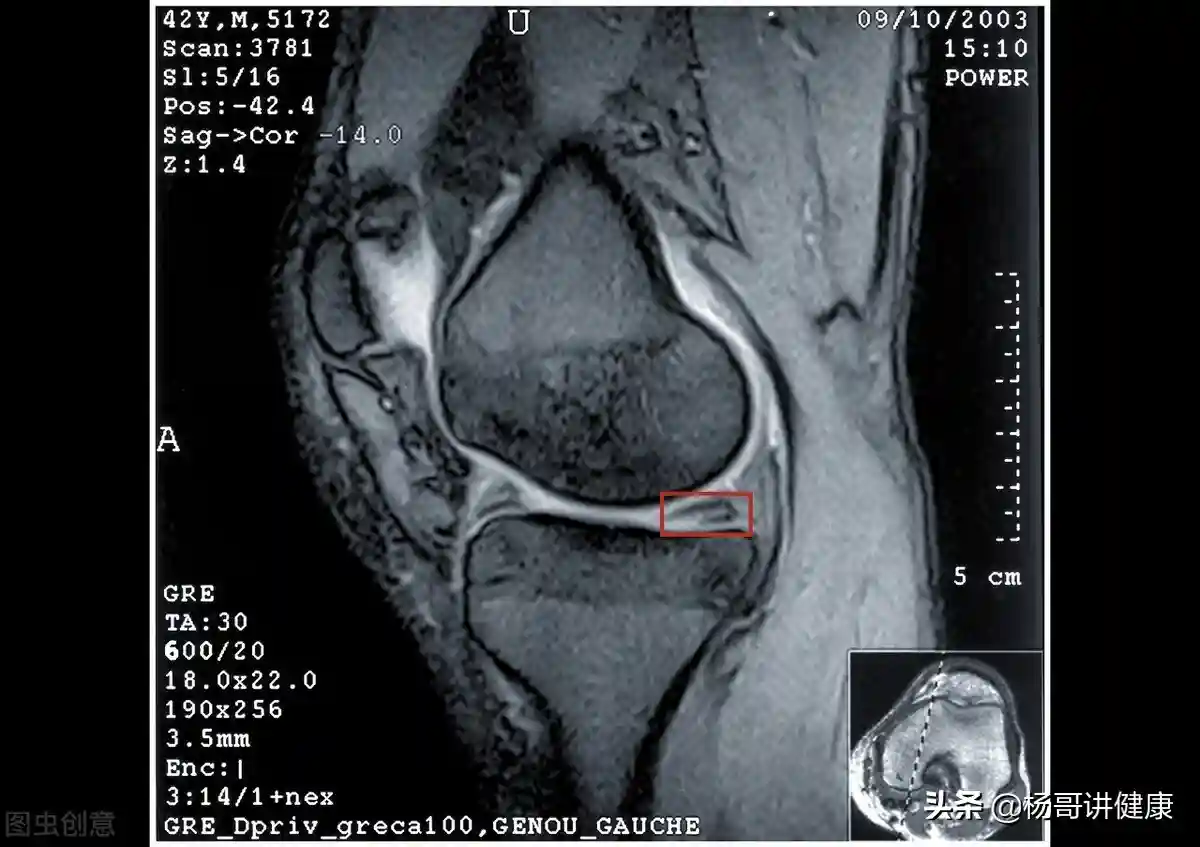

一位膝关节病患者发了一张膝关节核磁报告和膝关节核磁片子过来,然后云淡风轻地问我:请帮忙看一下我该怎么治疗?

这是我昨天的膝关节核磁,请您帮我看一下怎么治?

其实也很简单,如果你半月板三度撕裂,交叉韧带断裂,那么你做关节镜手术吧。或者还有滑膜皱襞肥厚之类,盘状半月板之类、膝关节软骨瘤之类,都会建议你手术。因为会越来越重啊。

如果显示较轻,那么说可以不手术,但可以做PRP,可以做干细胞。也可以打玻璃酸钠,吃氨糖,吃止痛药。